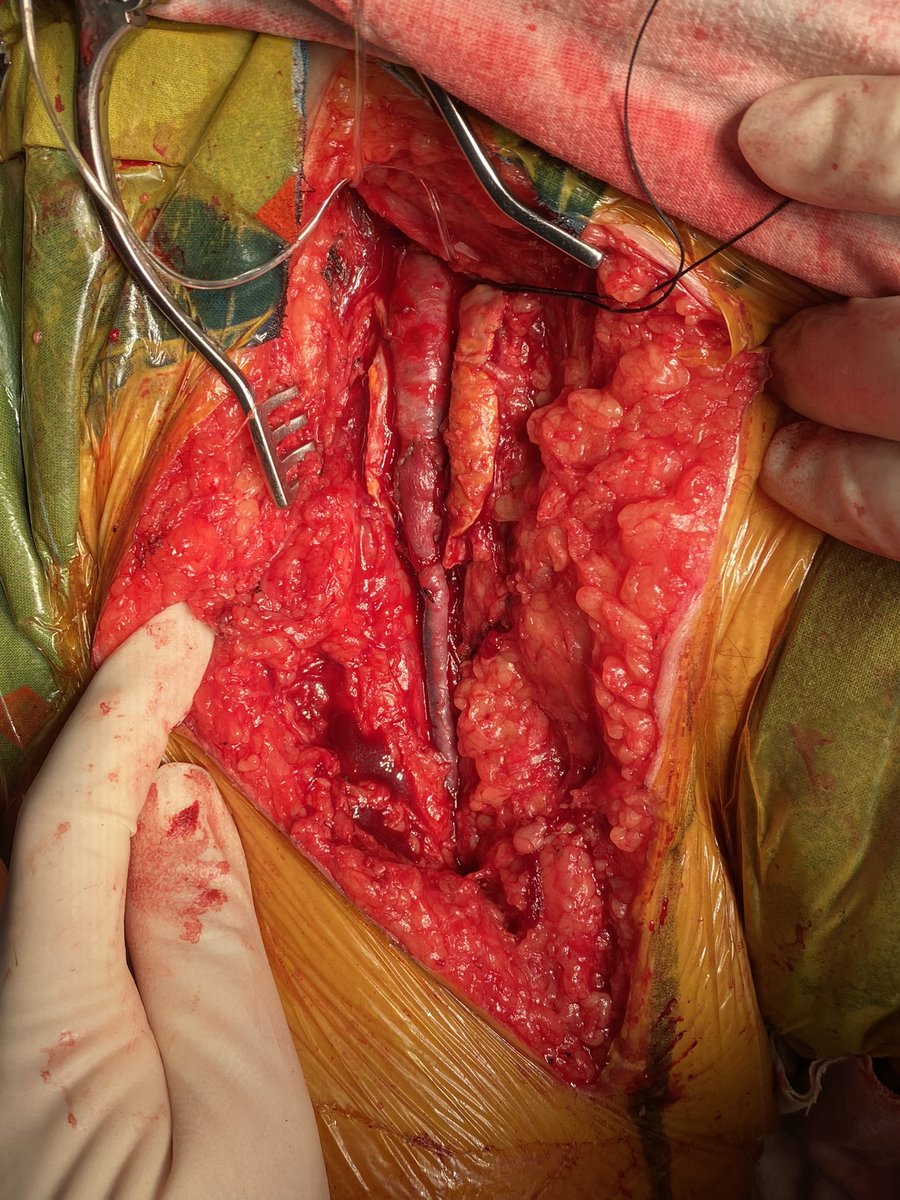

šŸŽÆCeliac artery occlusion from Median Arcuate Ligament Syndrome treated with ligament release alone. No bypass. No complex revascularization. Post-op CTA at 5 weeks shows sustained patency + complete symptom relief. šŸ‘‰ https://t.co/reC69RJmsx #MALS #VascularCompression

We present the case of an 18-year-old female diagnosed with Median Arcuate Ligament Syndrome (MALS) who presented with celiac artery (CA) occlusion. An open surgical approach was employed, the median...